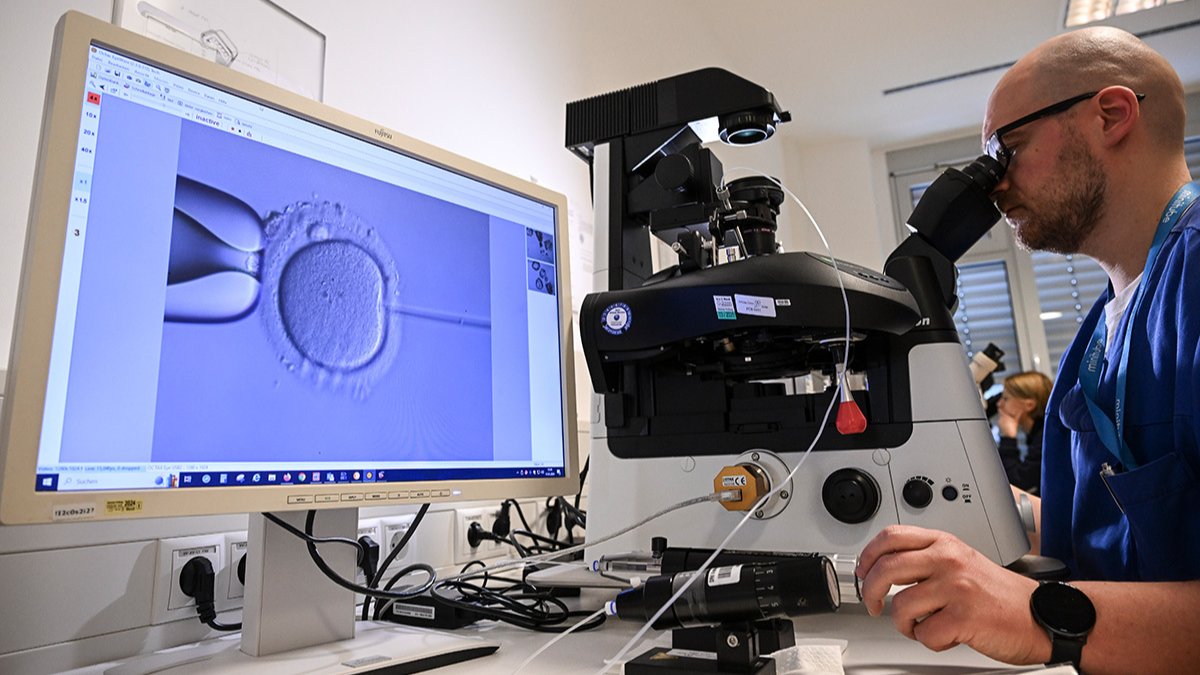

Суть технологии заключается в том, что оплодотворение яйцеклетки происходит не в организме женщины, а в лабораторных условиях, которые создаются с особой тщательностью, чтобы достичь нужного эффекта в случае, если он невозможен естественным путем.

Схематично это выглядит следующим образом. Женщине проводят гормональную гиперстимуляцию яичников, чтобы обеспечить созревание сразу нескольких яйцеклеток. Их извлекают с помощью пункции, отбирают наиболее жизнеспособные и помещают в чашку Петри — специальную емкость, содержащую суспензию сперматозоидов, в которой и происходит процесс оплодотворения. В течение суток в яйцеклетке формируются два клеточных ядра — пронуклеусы — мужское и женское. Как только они образуются, можно констатировать, что оплодотворение состоялось, а оплодотворенная яйцеклетка «превращается» в эмбрион.

В течение нескольких дней культуральная чашка с эмбрионом хранится в инкубаторе, в котором воссозданы такие же условия, как и в материнском организме: поддерживается такая же температура и уровень углекислого газа и кислорода. И именно здесь, в чашке Петри, начинает развиваться новая жизнь.

Сначала образуется содержащая полный двойной набор хромосом одна-единственная клетка — зигота, которая начинает быстро делиться. Уже спустя двое суток эмбрион состоит из четырех клеток, через трое суток — из восьми, на пятые-шестые сутки своего развития зародыш имеет сложную структуру, состоящую из почти 200 клеток двух типов: одни «отвечают» за образование плода, другие — за формирование плаценты. С этого момента деление клеток сопровождается ростом эмбриона.

Как правило, на третий-пятый день после оплодотворения производится перенос эмбриона в полость матки. В течение двух недель он должен «освоиться», прикрепиться к стенке матки и прижиться. Если это произошло, наступает беременность.